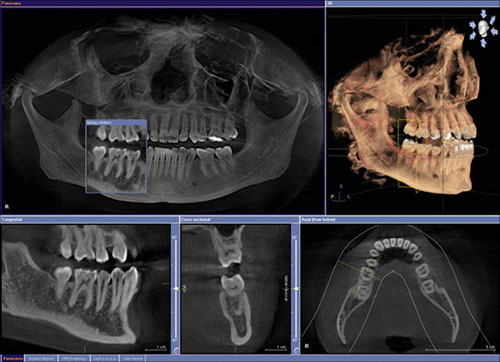

Si rilevano delle impronte e si eseguono della radiografie, normalmente una CBCT (Vedere sezione Imaging & Diagnostica) per definire la fattibilità dell’intervento e per programmarne la realizzazione.